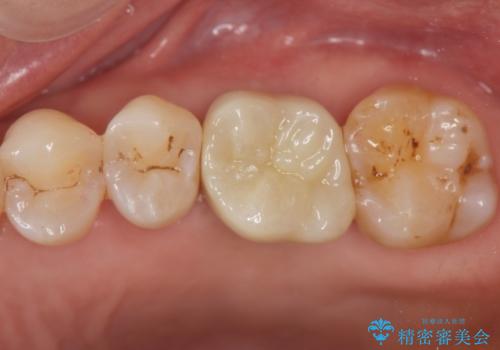

奥歯の欠損 インプラントによる咬合機能回復

- 奥歯を失い噛めないことの治療を希望され来院されました。

臨在する歯が虫歯もなく健全であるため、ブリッジではなくインプラントを用いた機能回復を計画します。

- 50万円(ストローマンインプラント・骨造成・チタンカスタムアバットメント・ジルコニアクラウン)費用は治療当時の料金となります

インプラントを用いることで、隣の歯を削ることなくしっかりと噛む機能を回復させることができます。